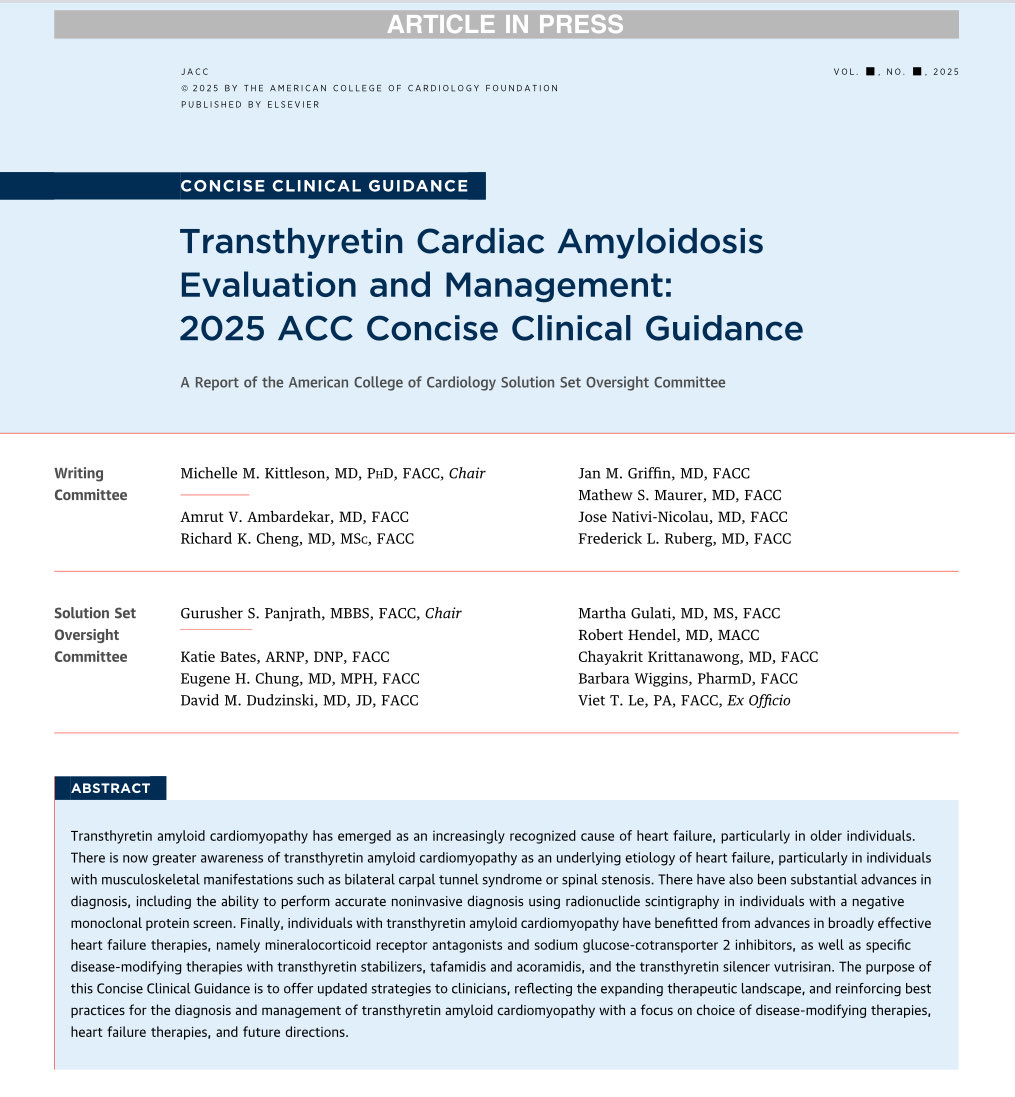

🔴 Transthyretin Cardiac Amyloidosis Evaluation and Management: 2025 ACC Concise Clinical Guidance @JACCJournals #Cardiology #CardioEd #Amyloidosis #FOAMed